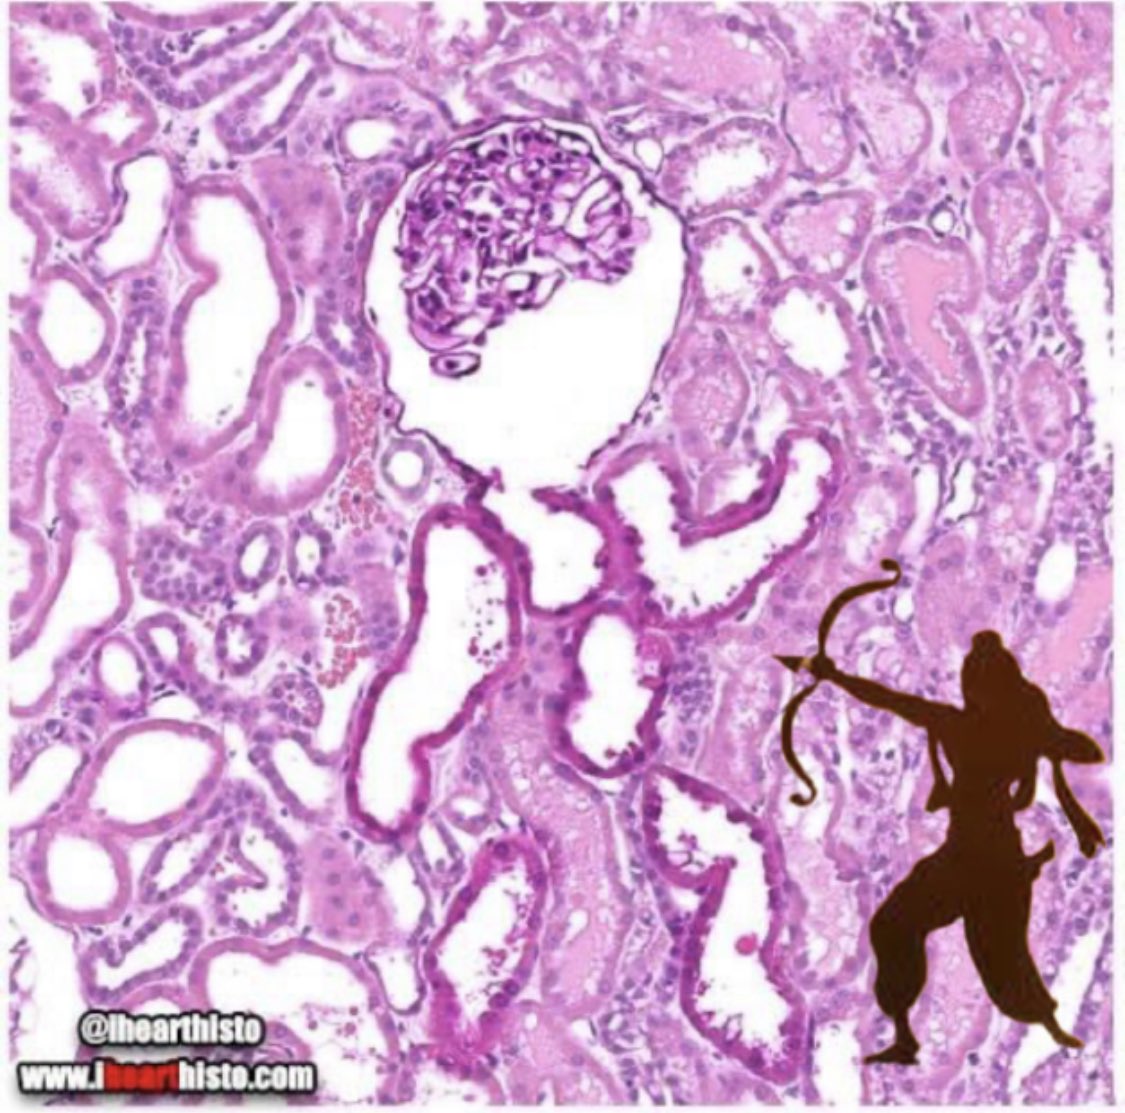

This is re(n)ally awesome!!! Well-written guidelines re: kidney transplant in myeloma et al by tour de force team: @vsanchorawala @LandauHeather #nelsonleung et al. Nice figures for #MMsm (stratify by 🐠 & MRD), MGUS, and SMM below. 🚨 MRD-neg *not* needed if standard risk.

Excellent guideline on how to think about kidney transplantation in patients with plasma cell disorders. - Aim for good disease control in standard-risk myeloma - Aim for MRD negativity in high-risk myeloma - Avoid IMiDs after transplant if possible - Reduce immunosuppression